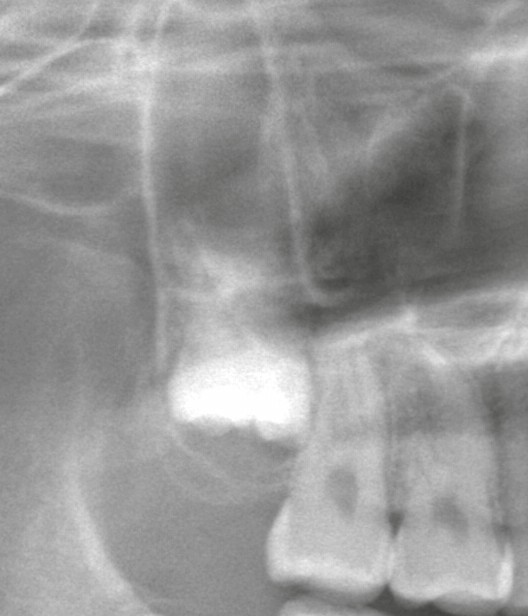

1|鼻のすぐ下にある上顎洞との距離が近いため

上顎の奥歯、とくに埋伏している歯は

上顎洞と非常に近い位置に存在します。

そのため、

* 骨を削る時の振動

* 上顎洞粘膜への軽微な刺激

* 血流の一時的な増加

これらが鼻腔側にも影響として出やすい構造になっています。

➡ 穿孔がなくても、翌日の軽い鼻血は珍しくありません。